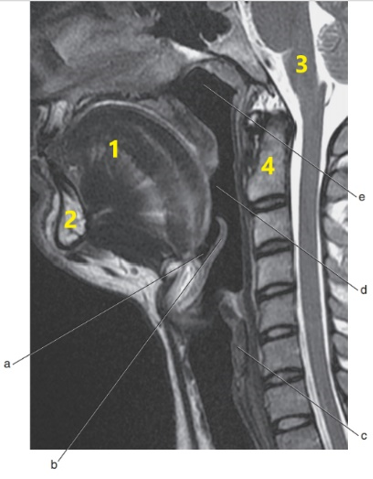

What anatomy is letter e ?

Nasopharynx

What is # 4 ?

C-1/C-2

What imaging plane is this ?

transverse

What anatomy is letter b ?

Epiglottis

Soft palate

What is # 3 ?

Brain stem